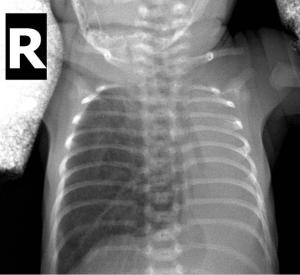

肺不张(atelectasis)应指出生后肺从未充盈过气体,而已经充气的肺组织失去原有的气体(eaeration)应称肺萎陷(pulmonary collapse)。但由于多年来沿用习惯,广义肺不张可包括先天性肺不张及后天性肺萎陷。肺不张表现为肺泡内不充气,引起肺泡萎陷。[1]